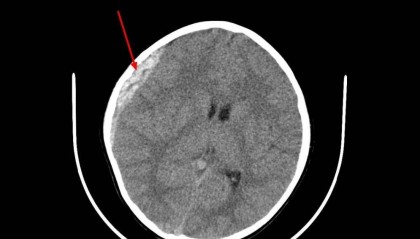

北京时间2月27日消息,18岁的北京国安梯队球员郭嘉璇2月6日在与西班牙球队的一场热身赛中被撞昏迷...